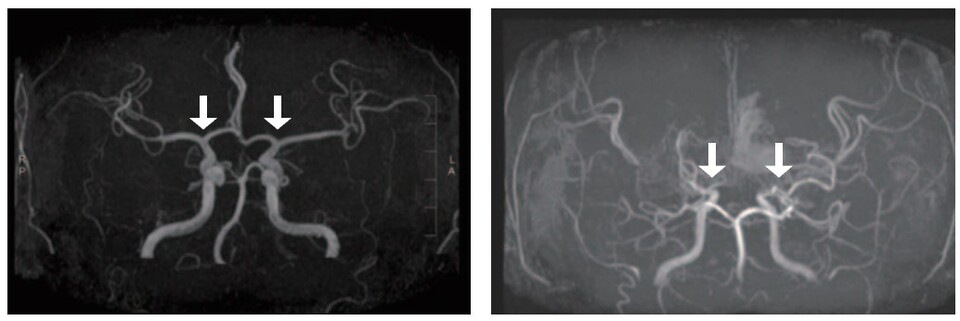

[ÀÇÇнŹ®·Àϰ£º¸»ç=±èÇö±â ±âÀÚ] Èñ±Í³Ä¡¼º ³úÇ÷°üÁúȯ ‘¼Ò¾Æ ¸ð¾ß¸ð¾ßº´’ÀÇ ±¹³» Ä¡·á ȯ°æÀÌ ÁúÀûÀ¸·Î Çâ»óµÈ °ÍÀ¸·Î ³ªÅ¸³ª ÁÖ¸ñµÈ´Ù.

ƯÈ÷ »ç¸Á·ü°ú ÇãÇ÷¼º ³úÁ¹Áß ¹ß»ý·üÀº Áö¼ÓÀûÀÎ °¨¼Ò Ãß¼¼¸¦ º¸¿´°í, Ä¡¸íÀû ÇÕº´ÁõÀÎ ‘ÃâÇ÷¼º ³úÁ¹Áß’ÀÌ ¾à 40% À¯ÀǹÌÇÏ°Ô °¨¼ÒÇß´Ù.

ÇÑÆí, Ä¡¸íÀûÀÎ ÃâÇ÷¼º ³úÁ¹ÁßÀº 2006³â 1000Àγâ´ç 3.3°Ç¿¡¼ 2021³â 2.0°ÇÀ¸·Î ¾à 40% À¯ÀǹÌÇÏ°Ô °¨¼ÒÇØ, ¼Ò¾Æ ¸ð¾ß¸ð¾ßº´ Ä¡·áÀÇ ÁúÀû Çâ»óÀ» º¸¿©Áá´Ù.